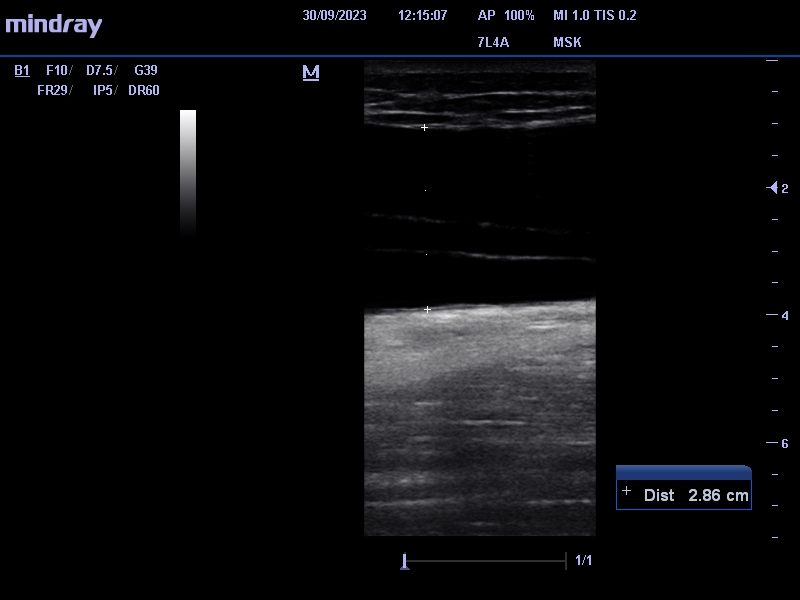

Se identifica entre el tejido celular subcutáneo y la fascia muscular, colección anecogénica, avascular de 2,8 x 17 cm (antero-posterior x craneocaudal) que nos sugiere lesión de Morel-Lavallée.

Ante la sospecha de LML se le deriva a urgencias hospitalarias para drenaje eco-guiado, le realizan punción-aspiración obteniéndose 345 ml de contenido serohemático. Posteriormente le  ponen vendaje compresivo.